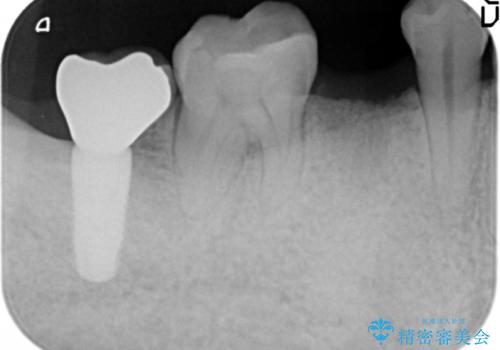

- 奥歯(右下5)のインプラントをご希望し来院された患者様です。

なるべく低予算でとのご希望により、アルファタイトインプラント(保証期間:3年)による治療を行いました。

インプラントの種類:アルファタイト

クラウンの種類:オールセラミッククラウン スタンダード